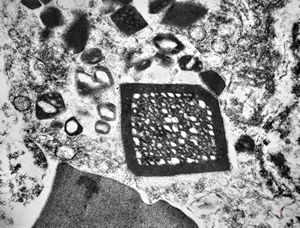

M,62y. | crystalline inclusion in endoplasmic reticulum - bone marrow, plasmocytoma

M,62y. | crystalline inclusion in endoplasmic reticulum - bone marrow, plasmocytoma

M,58y. | crystalline inclusions in hepatocyte after unknown medication

M,58y. | crystalline inclusions in hepatocyte after unknown medication